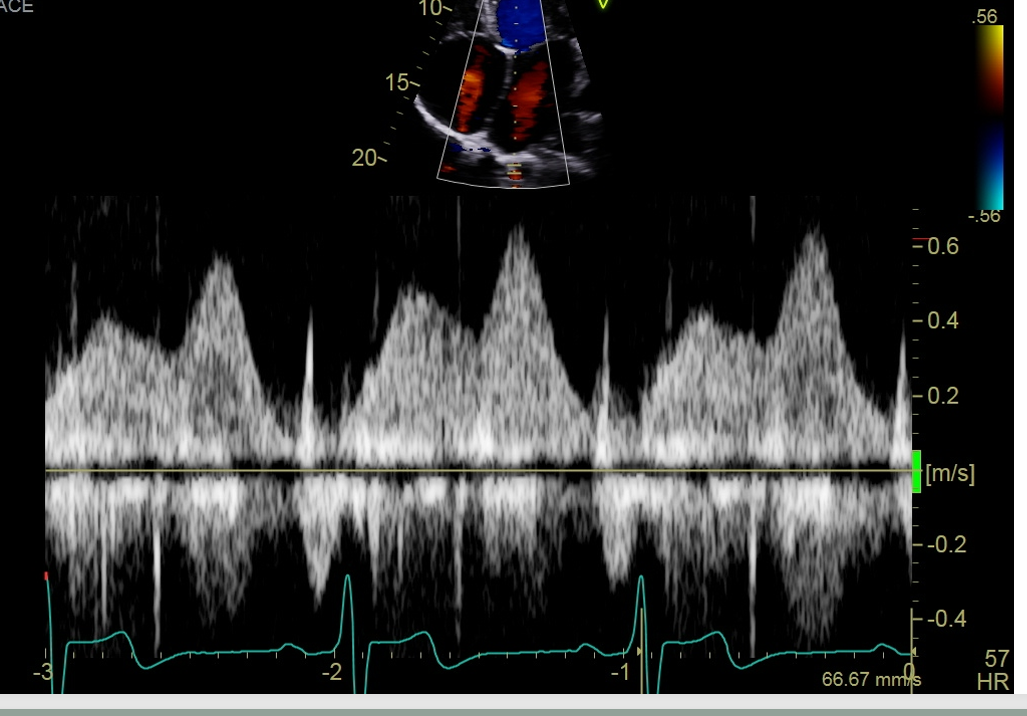

what single is this measurement for what are you going to peak, why would this doppler be important

this measure is for the pulmonary vein

Pulmonary vein peak systolic velocity (peak the S wave)

Peak D wave

peak the velocity of the atrial reversal or atrial duration

This will important when interrogate for MR, If the S wave is shorter than ourt D that is blunting so this coulf point to moderate or severe regurgitation if you see a reversal in these two